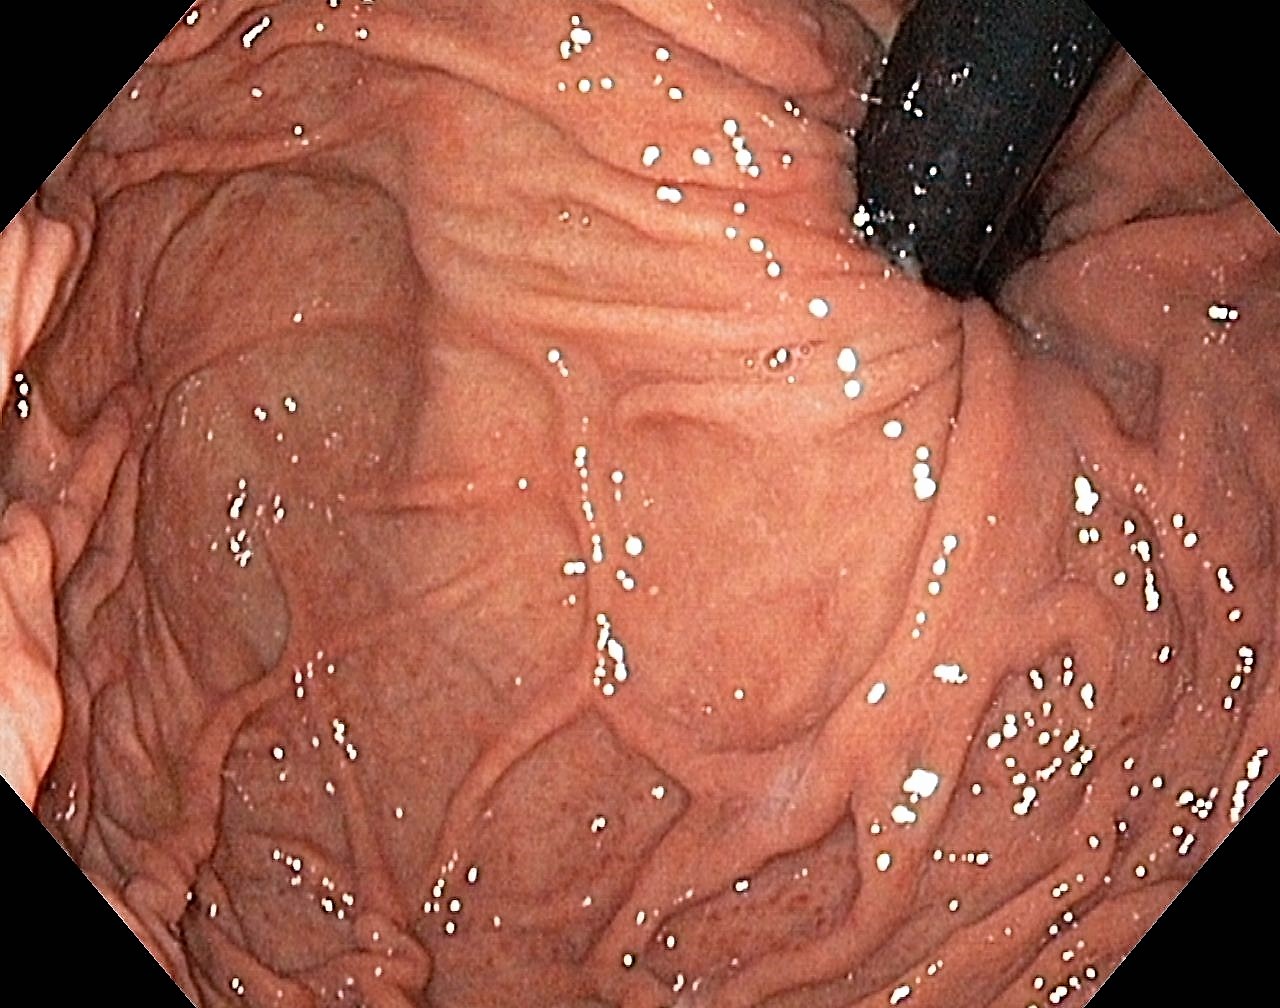

A Normal Gastric Fundus

A normal gastric fundus. Just click on a picture!